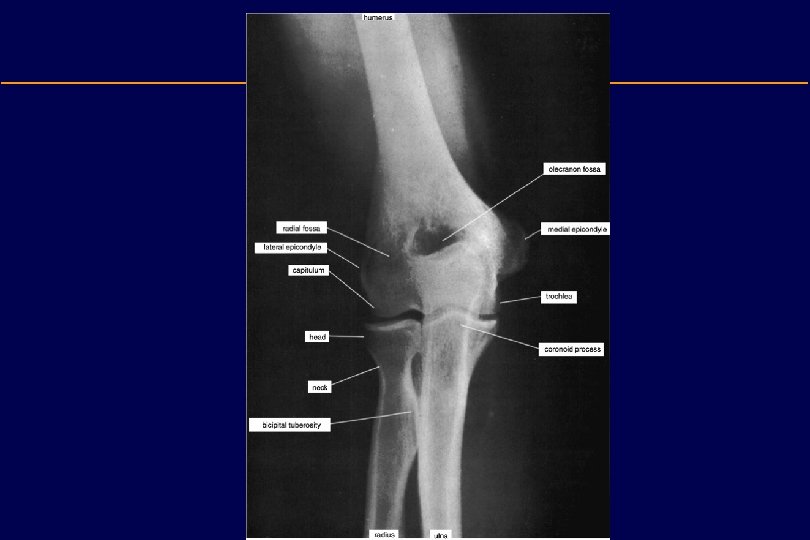

Distal Humerus • Medial epicondyle: – The pronator and flexor muscles of the forearm originate here • Lateral epicondyle: – The extensor and supinator muscles of the forearm originate here • Medial supracondylar ridge • Lateral supracondylar ridge • Trochlea (medial condyle): – Articulates with the trochlear notch of the ulna • Capitulum (lateral condyle): – Articulates with the radial head

Distal Humerus • Coronoid fossa: – Accommodates the coronoid process of the ulna during flexion. – A fat pad is situated here • Radial fossa: – Accommodates the head of the radius during flexion. – A fat pad is situated here • Olecranon fossa: – Accommodates the olecranon – A fat pad is situated here • Groove for ulnar nerve

Radius • The radius is the lateral and shorter of the two forearm bones. • Its proximal end consists of: 1. A short cylindrical (or thick disc like) head » The smooth superior aspect of the head of the radius is concave for articnlation with the capitulum of the hnmerus during flexion and extension of the elbow joint. » The head also articulates peripherally with the radial notch of the ulna » The head is covered with articular cartilage. 2. A neck » Relatively constricted between the head and the tuberosity. 3. A medially directed tuberosity » The oval radial tuberosity separates the proximal end of the radius from the body.